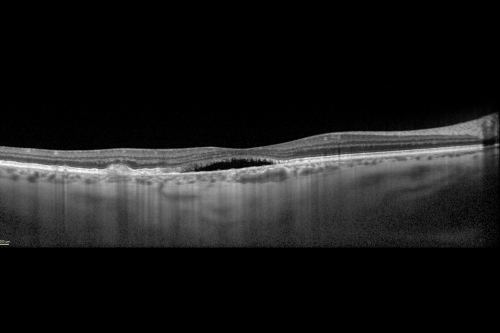

Cuticular Drusen (Basal Laminar Drusen) and Bilateral Chronic Subfoveal Fluid (Serous Retinal Detachment) unresponsive to monthly Avastin OCT OD EDI

OD 20/160,  Pinhole 20/80.   OS 20/63,  Pinhole 20/50.  OCT scan shows subretinal fluid with normal choroidal thickness.  Fluorescein angiogram shows cuticular/basal laminar drusen.  ICG shows no foci of choriocapillaris leakage.